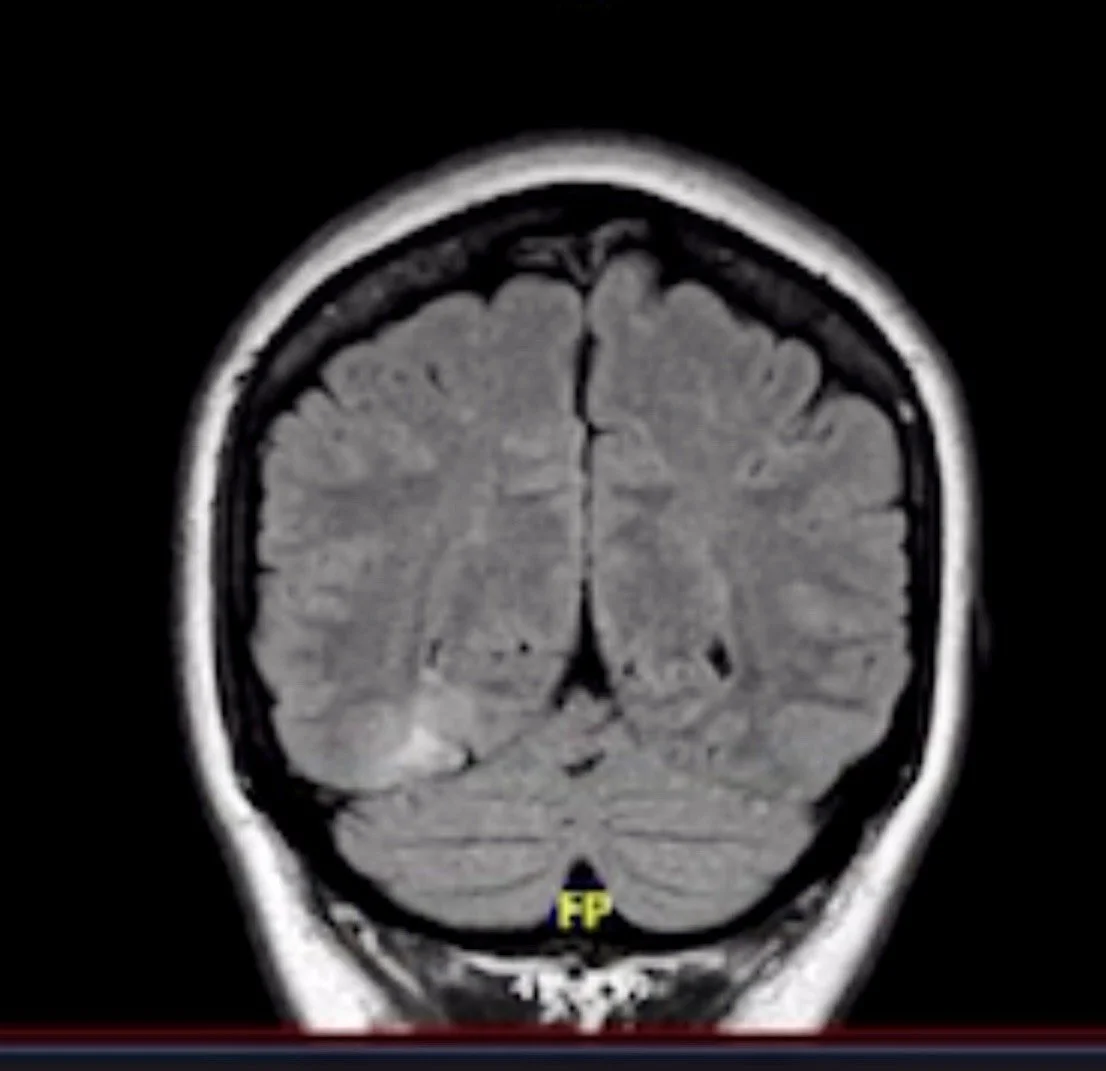

Her journey took an unexpected turn in 2022, when she was diagnosed with a brain tumor. Living with seizures and the realities of a disability could have silenced her, but instead, it deepened her calling. Melanie understood firsthand what it meant to feel overlooked, erased, or unseen by systems not designed to hold the fullness of her humanity.